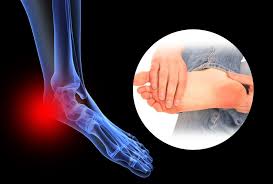

이 질환은 발밑의 족저근막에 염증이 생겨 발뒤꿈치에서 발가락까지 이어지는 섬유띠가 영향을 받는 질환으로, 중장년층 뿐만 아니라 젊은 세대에게도 흔하게 발생합니다.

족저근막염은 발바닥의 근막에 염증이 생기는 흔한 발목 문제 중 하나입니다. 이 질환은 다양한 증상을 동반하며 환자들에게 불편함을 초래합니다. 주요 족저근막염의 증상은 다음과 같습니다: